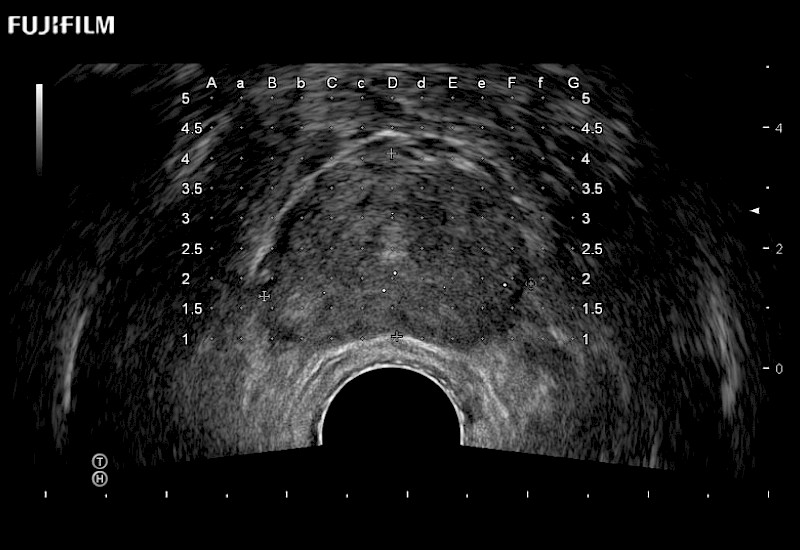

Exclusive 200° FOV end-fire prostate biopsy transducer.

Main Specifications: